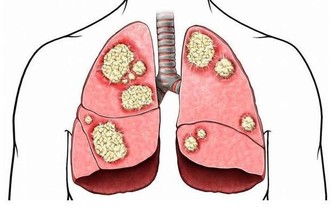

呼吸科醫生不希望你:過度裝修

許多哮喘患兒,其中不少要么是患兒媽媽懷孕時曾住新房,或者患兒出生後就搬入新房,

雖不能完全確定,但推測這兩者之間有一定關聯。

建議裝修時室內裝修簡單一些,越“豪華”可能污染越重;

少用地毯,以及布藝多的家具、飾品;

可採購空氣淨化器,定期淨化室內空氣。